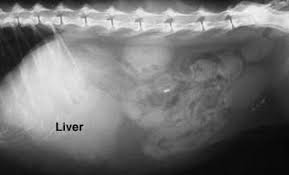

Symptoms Of Liver Cancer In Dogs - How To Treat Liver Disease In Dogs / The manifested cancer symptoms in dogs vary according to the affected portion.. Surgical removal of the tumor is recommended, when. Loss of appetite that can lead to weight loss. Get vaccinated against hepatitis b. The liver can regrow itself, so dogs can recover even if a large amount of the liver has to be removed, but the veterinarian will need to ensure the liver is functioning. The following symptoms of liver cancer in dogs are typically absent until the disease reaches an advanced stage hepatocellular carcinoma accounts for 50% of primary liver tumors found in dogs, while hepatocellular adenoma and hepatoblastoma are extremely rare.

Liver Cancer In Dogs Symptoms Diagnosis And Treatment Savory Prime Pet Treats from savoryprimepet.com Causes, symptoms, and treatment options for pets with liver cancer. Liver cancer in dogs is actually fairly rare with the condition affecting less that 1 1/2 percent of dogs. If your dog has a benign tumor the tumor will not spread and he will show no symptoms, unless it has ruptures or bleeds. Generalized illnesses, signs of jaundice, anorexia and vomiting, polyuria. As with all cancers, it is difficult to pinpoint a singular cause, as there are many genetic and environmental factors to consider. Cancer in dogs is just one cause of weight loss. Metastatic secondary dog liver cancer: Once the cancer progresses, dogs may show some of the following symptoms

Cancer in dogs is just one cause of weight loss. The symptoms of liver failure include ascites, jaundice, hepatic encephalopathy, and. Tumors that develop within the liver may be either benign (noncancerous) or malignant (cancerous). Surgical removal of the tumor is recommended, when. Causes, symptoms, and treatment options for pets with liver cancer. Our channel would be showing cancer symptoms, signs of breast cancer, horoscopo de hoy cancer, home remedy for cancer, natural remedies for cancer, foods for liver cancer, foods for skin cancer, foods for stomach cancer, foods liver disease problems in dogs treatment & homemade recipe. Fortunately, there are more treatments available for liver cancer in dogs than there were even five years ago. It is therefore difficult to diagnose. Liver cancer presents a special challenge because you may not notice any symptoms when the disease is starting and in its early stages. Generalized illnesses, signs of jaundice, anorexia and vomiting, polyuria. Liver cancer is suspected when the dog's serum chemistry profile shows increased levels of liver enzymes including alt, aspartate aminotransferase. In the united states, doctors usually discover signs of liver cancer when screening people for an underlying liver condition, such as chronic hepatitis. What causes liver cancer in dogs?

If your dog has symptoms of liver dysfunction, cancer may be suspected as the cause, based on age and the elimination of other factors. Your dog may show no signs of illness until the disease reaches an advanced stage. Symptoms of skin cancer in dogs common in dogs 7 years and older. Feeling very full after eating, even if the meal was small. Liver cancer in dogs is a tumorous growth in the lining of the liver, which is the organ responsible for removing toxins for the body, aiding in digestion, and helping with blood clotting. Loss of appetite that can lead to weight loss. An important note on your dog's cancer: Symptoms of liver cancer in dogs. Other common reasons include bad teeth, a poor diet, kidney problems, liver disease or gut problems. Be alert for coughing as one of the symptoms of lung cancer in dogs, but look for other clues. I think people are taking better and better care of their animals and pets are living longer and longer, so we're seeing more animals live to an age where they develop cancer. What causes liver cancer in dogs? As the true etymology of the disease is unknown, there is no known way to prevent liver cancer in dogs.

Https Encrypted Tbn0 Gstatic Com Images Q Tbn And9gctvdeiuti70tk1as 4c49y5g7vjvhijmmeoy5dmckyxx1kgyuer Usqp Cau from The manifested cancer symptoms in dogs vary according to the affected portion. Malignant liver tumors have been reported to metastasize to other organs such as regional lymph nodes, lungs. The characteristic symptoms of liver cancer include the medical expert either specifically extracts out the cancerous tissue mass within the liver or removes the entire liver affected by cancer, in order to prevent the spread of the malignant tumour to other organs. Liver cancer in dogs is actually fairly rare with the condition affecting less that 1 1/2 percent of dogs. Symptoms of liver cancer in dogs can be vague and indistinct, such as appetite loss, lethargy, and vomiting. Loss of appetite that can lead to weight loss. Metastatic secondary dog liver cancer: The hepatitis b vaccine is recommended for all infants at birth and for adults who.

The liver fails to function because of liver cancer in dogs. The hepatitis b vaccine is recommended for all infants at birth and for adults who. The liver can regrow itself, so dogs can recover even if a large amount of the liver has to be removed, but the veterinarian will need to ensure the liver is functioning. Canine liver cancer can be primary (originated in the liver) or metastatic (originated somewhere else and spread to the liver). Hemangiosarcoma is a type of tumor in the blood vessels located in the spleen or liver (aka liver cancer in dogs). Symptoms of liver cancer in dogs can be vague and indistinct, such as appetite loss, lethargy, and vomiting. Liver cancer, according to who, is among the ten most common malignant tumors in the world. You can lower your risk of getting liver cancer in the following ways—. What are some of the symptoms of cancer in dogs? Liver cancer symptoms may include—. Your veterinarian may run laboratory tests to look for signs of primary liver cancer in dogs sounds like a terrifying diagnosis, but the upshot is that the liver can regenerate, even if a large portion is removed. Other common reasons include bad teeth, a poor diet, kidney problems, liver disease or gut problems. Causes, symptoms, and treatment options for pets with liver cancer.